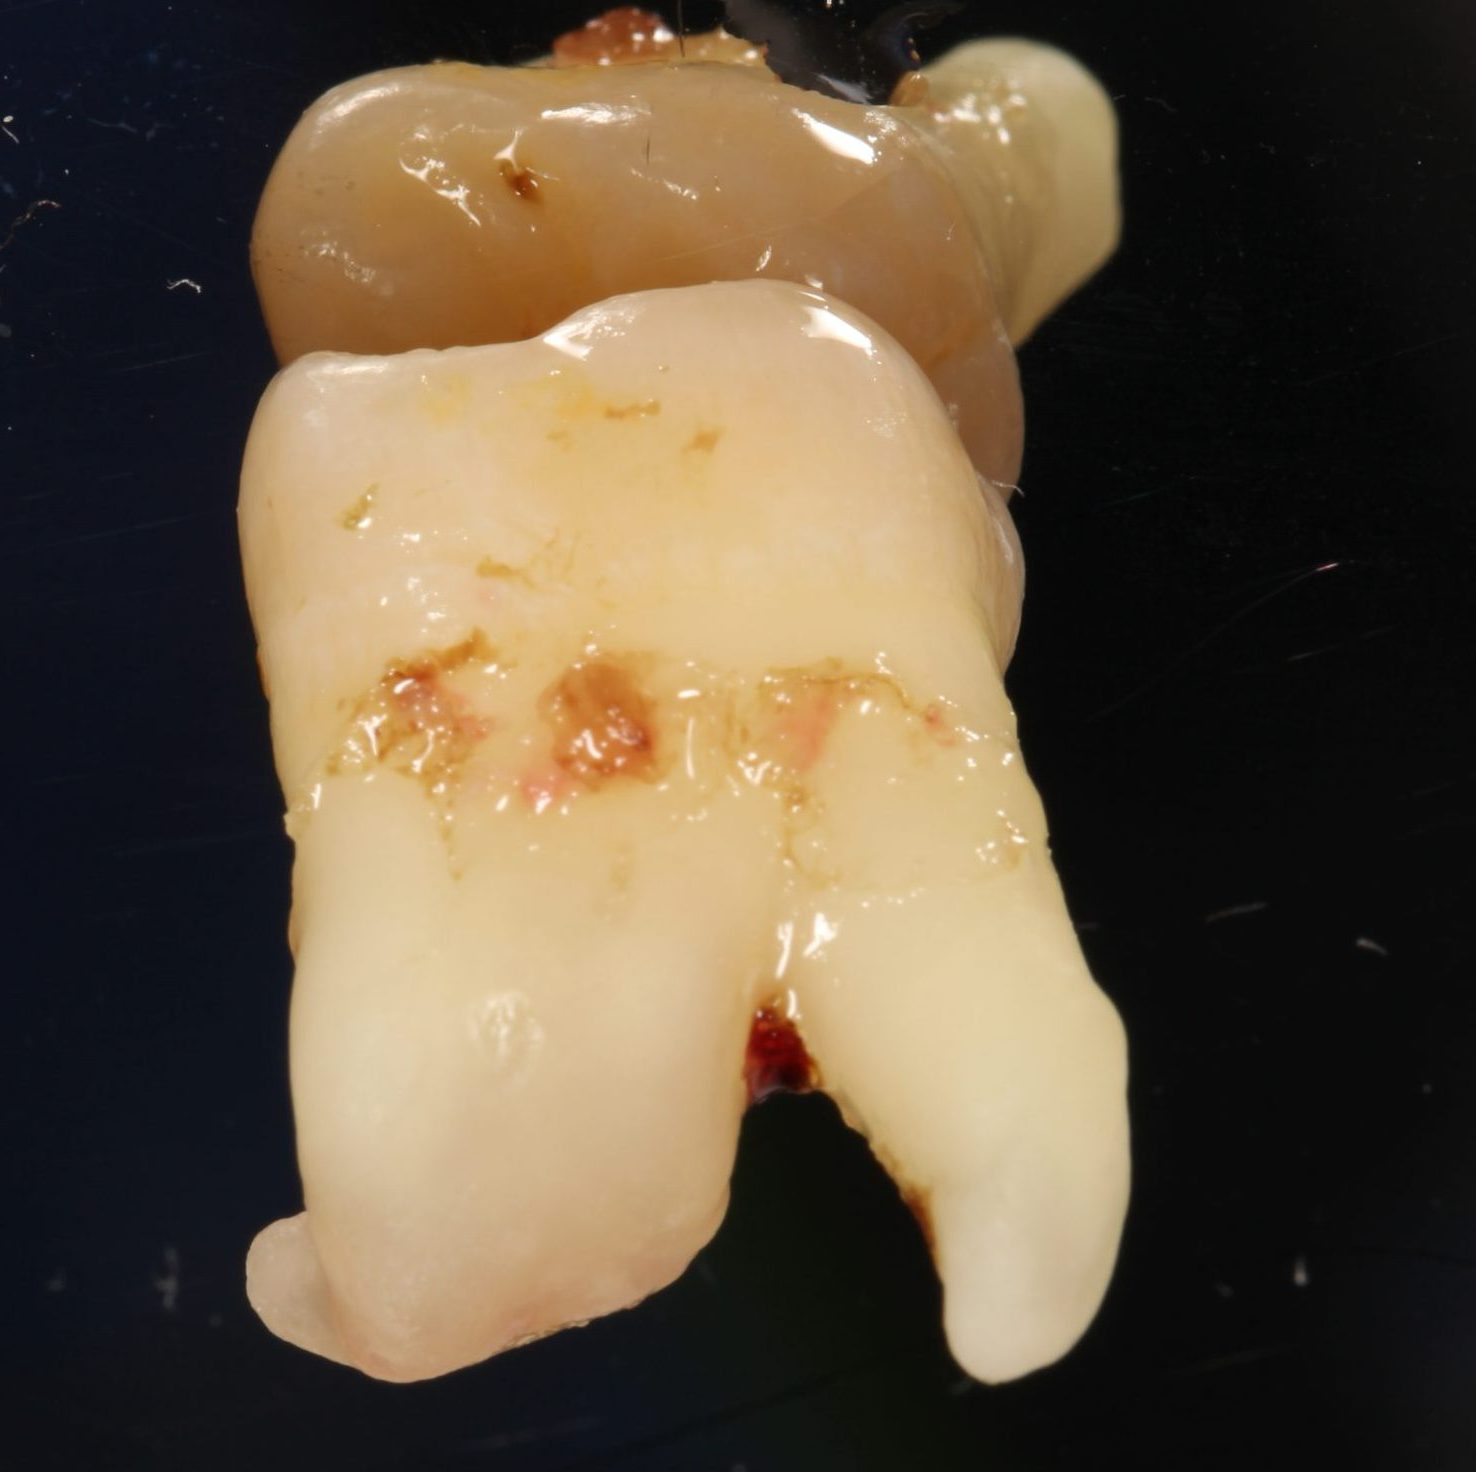

Wisdom tooth Cavity Causing Pain

28 year old male patient experienced severe pain because a large cavity reached the nerve in his upper wisdom tooth.  Both lower and upper wisdom teeth were extracted in the same appointment.  The lower wisdom tooth was sectioned so it could be removed.